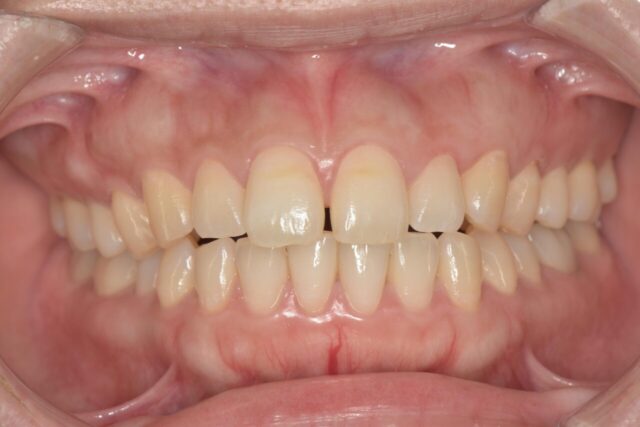

そしてインビザラインが終了し、オープンバイトだった前歯がしっかりと噛むようになりました✨

この方はオープンバイトの程度が分かりづらいですが、分かりやすい症例でご覧下さい😊

この方も見た目では歯並びが綺麗に見えますよね。下から見た写真を比較すると…

下から見るとオープンバイトなのが良く分かります!

この方も同じようにインビザラインで矯正し、前歯も奥歯も当たる正しい噛み合わせに✨